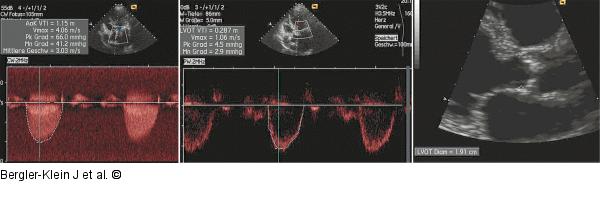

Abbildung 3: Aortenklappenöffnung 73-jährige Patientin: Bestimmung der Aortenklappenöffnung nach der Kontinuitätsgleichung. Diese beruht auf dem Prinzip: Der Fluss im linksventrikulären Ausflusstrakt (LVOT) muss gleich sein wie der Fluss über die Aortenklappe (AK). Die benötigten Variablen sind das Velocity-Time-Integral des LVOT (PW-Doppler) und der Aortenklappe (CW-Doppler), sowie der Durchmesser des LVOT. Die Aortenklappenöffnungsfläche (KÖF) errechnet sich aus der Formel: KÖF = (LVOT Diameter2 × 0,785 × LVOT VTI)/ Aortenklappen VTI. Es liegt mit einer Vmax des AK-Jets von 44,06 m/s und einer errechneten KÖF von 0,74 cm2 eine wirksame Aortenklappenstenose vor. |